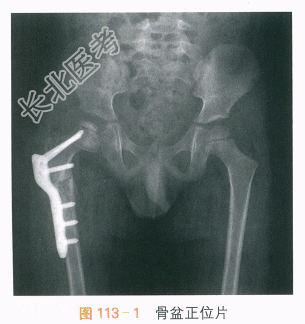

X线片提示:右股骨头骨骺形态欠光整,干骺端“杯口状”凹陷伴不规则高密度影,右侧股骨截骨术后,内固定在位,截骨线可见,如图113-1所示。